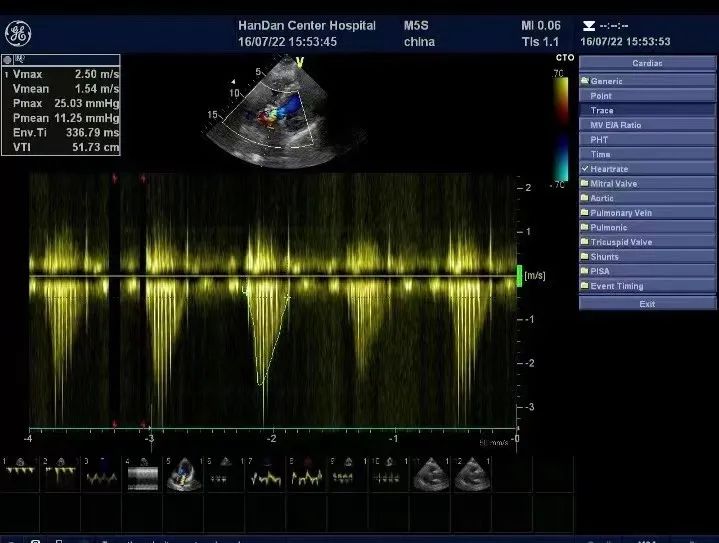

术后超声:峰值流速2.5m/s,跨瓣压差11mmHg

手术过程顺利,麻醉效果满意,术后患者安返ICU。患者的平均跨瓣压差由术前的83mmHg改善至术后的11mmHg, 主动脉瓣瓣口峰值流速由术前的5.8m/s改善至术后的2.5m/s,患者获益明显。